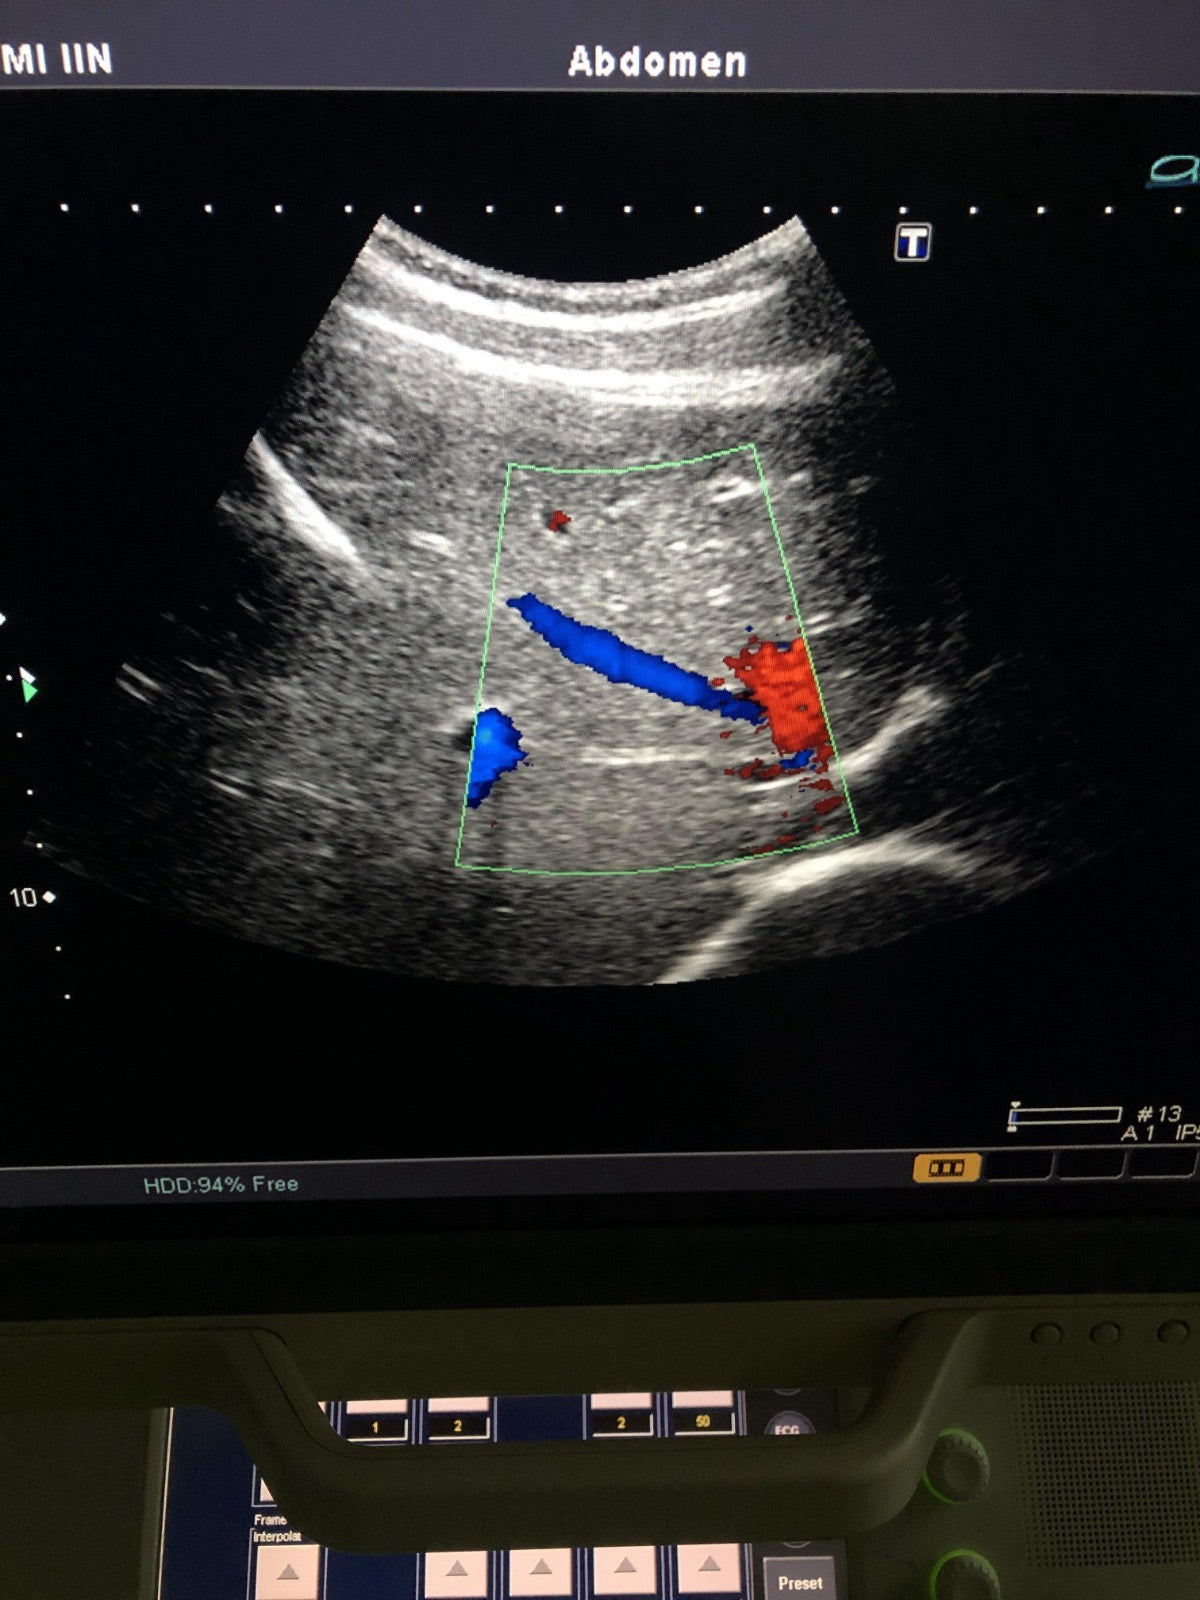

Toshiba canvex array biopsy transducer probe

Model number: PVT-350BT

SN: 99A09Y2458

MFG date: 2009/11

probe condition you can see in pictures